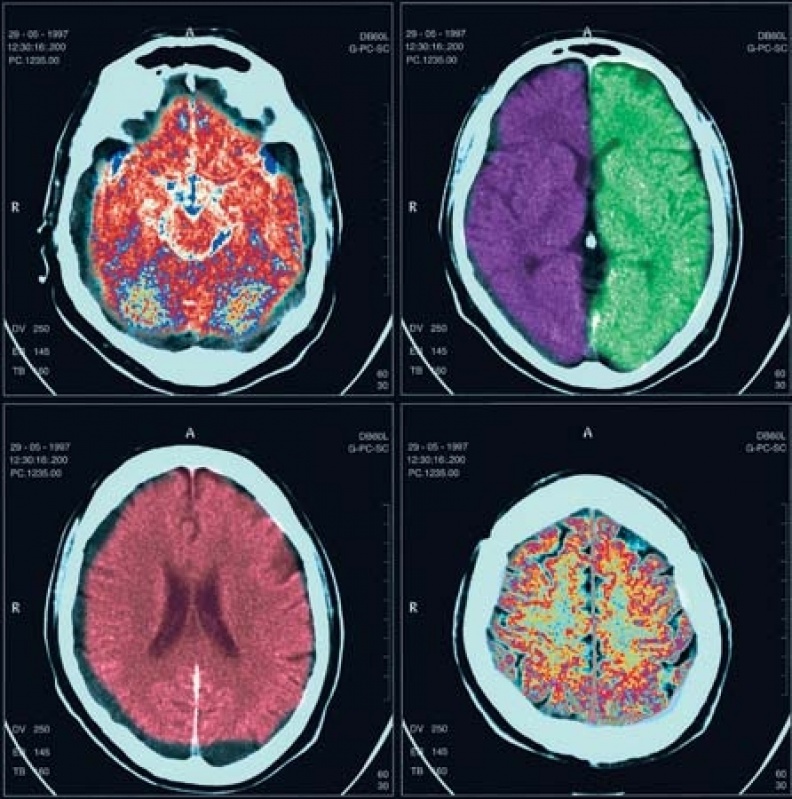

Medicom ExamesTomografia Computadorizada permite o médico iniciar um tratamento entendendo da real doença ou localização precisa da fratura de seu paciente, uma... Cotar Agora Saiba Mais

Medicom ExamesExames de tomografia torna possível ao médico começar um tratamento entendendo a real doença ou localização exata da fratura de seu paciente, já... Cotar Agora Saiba Mais

Medicom ExamesExame de tomografia computadorizada em São Paulo permite aos pacientes diagnosticar diferentes tipos de doença, podendo logo receber o tratamento... Cotar Agora Saiba Mais

Medicom ExamesExame de tomografia computadorizada permite visualizar órgãos e ossos dos pacientes em alta definição, isso possibilita entender o real... Cotar Agora Saiba Mais